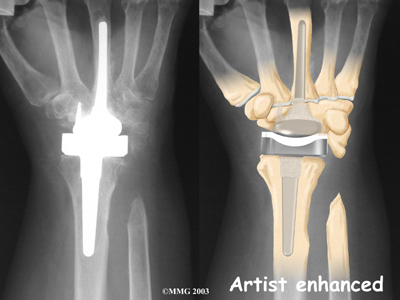

Modern artificial wrist joints are made of metal and plastic. The part that fits against the end of the radius bone of the forearm is called the radial component. It is made up of two pieces. A flat metal piece is placed on the front part of the radius. It has a stem that attaches down into the canal of the bone. A plastic cup fits onto the metal piece, forming a socket for the artificial wrist joint.

The part that replaces the small wrist bones is called the distal component. This piece is made completely of metal. It is globe shaped to fit into the plastic socket on the end of the radius. The metal distal component is attached by two metal stems that fit into the hollow bone marrow cavities of the carpal and metacarpal bones of the hand.

The plastic used in artificial joints is tough and slick. It allows the two pieces of the new joint to glide easily against each other as you move your wrist. The ball and socket allow movement of the wrist in all directions.

Cemented into Place